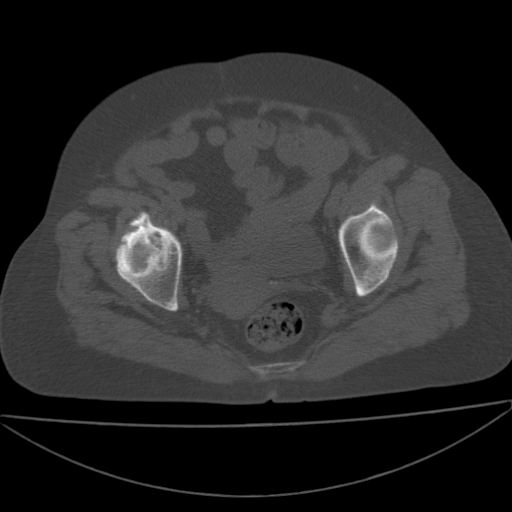

以下是引用余辉在2009-4-23 17:08:00的发言:[br]考虑右髋关节退行性变.股骨颈改变考虑陈旧性骨折可能,股骨头顶部关节面下似有透亮区,股骨头皮质环增厚,考虑有股骨头坏死

以下是引用王显瑞在2009-4-23 16:45:00的发言:[br]考虑股骨颈陈旧性骨折,股骨头缺血型坏死